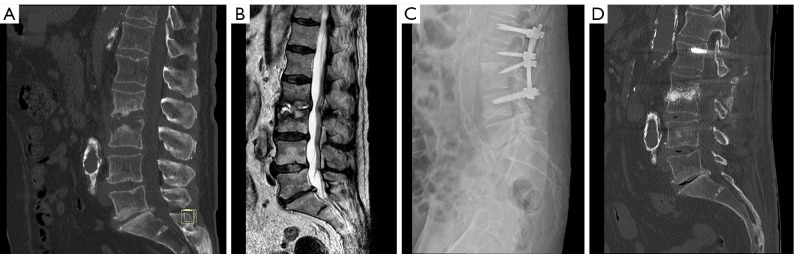

The article aims to describe the novel surgical technique of filling anterior spine cavitations in pyogenic spondylodiscitis (PS) using bioactive glass S53P4 (BAG-S53P4) (BonAlive®) in association with posterior spinal stabilization alone and its results in the first three patients. The technique starts with a posterior approach and instrumentation of the spine, total or partial laminectomy (when needed), debridement of the intervertebral space and cavity filling with BAG-S53P4, without any additional anterior instrumentation (i.e., meshes/cages). We retrospectively reviewed the first three cases of spondylodiscitis surgically treated with this technique at the department of orthopaedic surgery of the ASST-Ovest Milanese, Legnano Hospital (Italy). Functional outcomes, pain level, and C-reactive protein (CRP) trends were reported. Serial plain radiographs were collected, and a computed tomography (CT) scan was performed after a period of 2-3 years. A rapid improvement and healing from infection were observed in all cases with progressive spinal fusion and restoration of the previous quality of life. We did not observe major adverse events. BAG-S53P4 can be safely introduced in the disk space through a posterior approach to fill vertebral cavitation when the posterior wall is almost intact. It may be considered a safe and useful biomaterial in the surgical treatment of spondylodiscitis, helping in the eradication of the infection and promoting progressive spinal fusion. With this technique, anterior instrumentation and double approaches could be avoided in case of limited bone defects and moderate spinal deformity.

Abstract Image